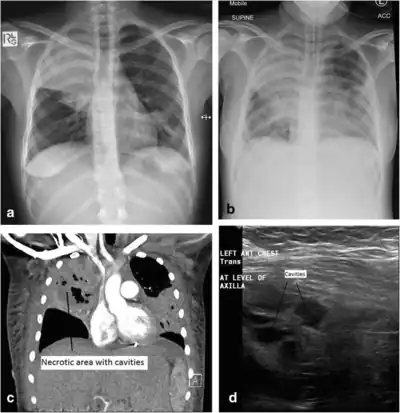

Additional imaging

a) Initial plain chest radiograph showing a dense right upper zone airspace opacity and lingula airspace changes, consistent with multi-focal pneumonia. The following images were performed 24 h later. b) Plain chest radiograph with the patient intubated and ventilated revealing cavitation in the right mid to upper zones, pleural effusion and more general airspace changes bilaterally. c) Computed tomography (CT) scan, coronal view, demonstrating non-enhancing area (necrotic) thin-walled cavities within the right upper lobe and lingula. d) Lung ultrasonographic image displaying thin-walled cavities in the lingula region of the left lung. And this needs even more clarification.[note 1]